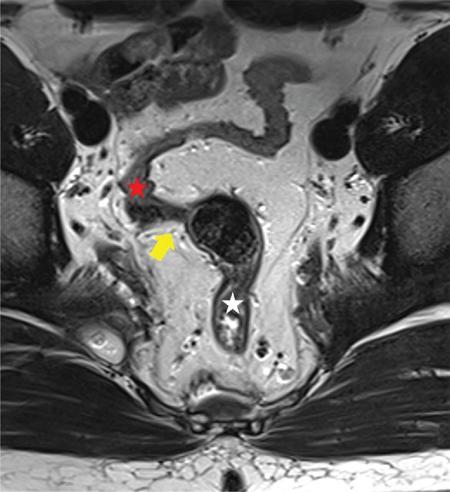

Sumit Mukhopadhyay, Saugata Sen, Aditi Chandra, Argha Chatterjee, Priya Ghosh, Anisha Gehani Cloaca is the part of hindgut caudal to the attachment of the allantoic diverticulum. It divides into a broad anterior urogenital (vesicourethral and urogenital sinus) part and a narrow posterior anorectal compartment/primitive rectum, separated by the urorectal septum. This anorectal compartment gives rise to mid rectum and lower rectum and upper part of anal canal proximal to dentate line. The peritonealized upper part of rectum develops from hindgut proximal to cloaca. The distal most part of anal canal below the dentate line develops from invaginated ectoderm known as proctodeum (Fig. 8.5.1). Initially during development, the rectum is suspended from the posterior abdominal wall by a mesentery, along with the rest of the gut. After completion of rotation of the gut, rectal mesentery fuses with the posterior abdominal wall, majority of rectum becomes retroperitoneal and hindgut mesentery is seen as mesorectum. The artery of the hindgut is inferior mesenteric artery. Anatomically, classically taken as 6 inches (approximately 15 cm), or beginning at the level of S3 vertebra. Surgically defined as 15–18 cm from anal verge (AV), thus anal canal and rectum are considered together for the purpose of surgical and radiological anatomy, though management differs in cases of rectal adenocarcinoma and anal squamous cell carcinoma (SCC). Various trials on rectal cancer neoadjuvant therapy have taken different lengths of cut-off for rectal cancer starting from AV: 9 cm, 12 cm, 15 cm or 16 cm (Table 8.5.1). Rectum continues as sigmoid colon superiorly. The point of transition between rectum and sigmoid colon is controversial. Anatomically, this is the point where sigmoid mesocolon ends, appendices epiploicae are lost and taenia coli gradually converge and disappear. There is no single transition point between these features. These features are not visible to the radiologist/endoscopist as well. Several features defining rectosigmoid junction/transition are variously accepted by different radiologists: Rectum continues as anal canal, which opens to the exterior at AV (mucocutaneous junction). Anorectal junction (ARJ) is considered to be the point at which the angle of the long axis changes, and corresponds to the upper border of puborectalis muscle. The change in axis of anal canal and rectum is well visualized on sagittal MRI. Dentate line lies along the anal crypts (the openings of anal glands), and vertical folds called columns of Morgagni extend superiorly from the dentate line. Anatomists consider the dentate line to be the landmark for ARJ, but the dentate line lies distal to the puborectal sling, and this definition is not clinically relevant. Anal canal is directed posteroinferiorly. At ARJ, the long axis of rectum changes so that it is directed anteroinferiorly. Mid rectum and upper rectum follow the sacral concavity, and the long axis of rectum is again directed posteroinferiorly. Upper rectum is frequently mobile and may not be in midline. Three incomplete folds consisting of mucosa, submucosa and circular muscles, named as Valves of Houston, are seen within the lumen of rectum during endoscopy, but these are not visualized radiologically. The middle valve is roughly at the level of anterior peritoneal reflection, and the superior most valve is at the level of rectosigmoid junction. Surgically and radiologically, rectum is divided into thirds: lower third, middle third and upper third (Table 8.5.2). Most commonly, this division is according to distance or length from AV. Lower third is 0–5 cm, middle third is 5–10 cm, upper third is 10–15 cm from AV (Fig. 8.5.6). Some radiologists define low rectum as 6 cm or less from AV, mid rectum as 7–11 cm and upper rectum as 12–15 cm. The justification of defining low rectum as 6 cm or less from the AV is that, management of most of the tumours at this location suffers from surgical challenges due to tapering of mesorectum and proximity of other pelvic structures. These tumours have a higher rate of CRM positivity, abdomino-perineal resection (APR) and permanent stoma, higher rates of recurrence and mortality, poor function of stoma after sphincter preservation. Another way of defining low rectum, surgical management of which differs from the upper two-thirds, is the portion lying distal to the proximal origin of levators at pelvic side wall. This definition was provided by the English National Low Rectal Cancer Development Programme (LOREC) and is best visualized in the coronal plane by a line joining proximal origins of levators at pelvic side walls (Fig. 8.5.7). ARJ is an important landmark in the management of rectal cancer. Distance between lower border of the tumour and ARJ is important for treatment planning. ARJ is defined as the point at which puborectalis fuses with the levator muscles, and the long axis of rectum changes from anteroinferior to posteroinferior at this point. Its upper extent begins few centimetres above the dentate line, and its length varies from 2–5 cm from AV. Histologically the proximal end of the anal canal is the point at which the columnar epithelium of the rectum becomes the transitional epithelium. Anal canal mucosa has several longitudinal columns, known as anal columns, which end at the dentate line. Below the dentate line the mucosa is smooth and transitions into skin at AV. Approximately at the level of dentate line, the internal anal sphincter (IAS) ends, and the smooth mucosa leads to the intersphincteric plane, distal to which the external anal sphincter extends up to the AV (Fig. 8.5.8). Upper third of rectum is anteriorly covered by peritoneum. Peritoneal covering gradually widens superiorly till it is covered by peritoneum on all sides at the level of sigmoid colon. The exact level of peritoneal reflection varies between individuals, and is quite often seen in axial and sagittal MRI. In axial T2-weighted MRI, a thin hypointense layer with V-shaped attachment to anterior rectal wall is seen representing the anterior peritoneal reflection. This is known as the ‘sea-gull’ sign. Mesorectum and mesorectal fascia (Fig. 8.5.10): lower two-thirds are surrounded by extraperitoneal fat and connective tissue known as mesorectum, which contains lymph nodes, nerves and blood vessels (descending branches of superior rectal artery and corresponding veins). Mesorectal fat is contained within a thin layer of fascia, known as mesorectal fascia (MRF). MRF separates mesorectal fat from extra mesorectal tissues of the pelvis. A relatively avascular plane of areolar tissue lies between MRF and parietal pelvic fascia, facilitating surgery. Importance: Assessment of structures within mesorectum is important for staging and prognostication of rectal cancer. Mesorectal node involvement is N disease. Tumour extension within mesorectal vessels is known as extramural vascular invasion (EMVI) and is thought to be associated with higher chances of vascular dissemination and distant metastases. MRF forms the boundary of the surgical excision plane in total mesorectal excision (TME) – the standard surgery for rectal cancers at present. It is important to understand the various fascial reflections of the pelvis in order to understand pathways of disease spread. The plane between the MRF and the pelvic fascias is the surgical plane. Posteriorly, covering the sacrum, presacral venous plexus and hypogastric nerves, lies the presacral fascia. It fuses with MRF inferiorly at the level of levator ani muscle. The space between presacral fascia and MRF is known as the retrorectal/rectosacral/pelvirectal space, and that between the sacrum and presacral fascia is the presacral space. The presacral fascia continues laterally as the parietal pelvic fascia which covers the lateral pelvic wall. It has two lamellae which encase the pelvic visceral nerves as they course forward from the sacrum to the anterior pelvic organs. The rectosacral fascia/Waldeyer fascia, called as rectosacral ligament by anatomists, is a thickening arising from presacral fascia and running forward to meet the MRF. This divides the rectosacral space into a superior and an inferior compartment, communicating with each other. In males, anteriorly, between the rectum and prostate-seminal vesicles, lies the rectoprostatic fascia/Denonvillier fascia. It is difficult to distinguish from the closely related MRF, and carries the hypogastric nerve and vascular branches to the prostate and male genital organs. In females, anterior to the MRF, lies the rectovaginal septum. According to most views, this septum consists of two layers. The anterior layer corresponds to Denonvillier fascia, and extends from the pelvic floor to the posterior wall of vagina and uterus. The posterior layer is in close relation to the MRF, runs from the pelvic diaphragm and ascends to the peritoneal reflection before fusing with the rectal wall. The lateral rectal ligaments are controversial structures as they are not visualized by imaging and may not carry important structures such as nerves and vessels. However, in some cases, the middle rectal artery may run through them and the accompanying lymphatics may provide a pathway between mesorectal and extra mesorectal lymph nodes. In females, the pelvic floor may be considered to have three compartments, anterior compartment containing bladder and urethra, middle compartment containing the vagina and the posterior compartment containing the rectum. These compartments are supported by the endopelvic fascia and levator ani muscle. The levator ani has several compartments, of which the two most important ones are the iliococcygeus and puborectalis. The iliococcygeus starts as the same fibres as the EAS, and then fans out as a sheet to insert at the pelvic sidewall at the tendinous arch. Posteriorly these fibres fuse in the midline to form the levator plate/raphe. The pubococcygeus and puborectalis are considered together as pubovisceralis muscle. It inserts lateral to the symphysis pubis anteriorly, and forms a sling around the rectum, pulling it anteriorly. Components of the levator ani can be identified in T2-weighted MR images. In males, there are two compartments, anterior containing bladder, urethra, prostate and seminal vesicles and the posterior compartment containing the rectum. Pubococcygeus consists of pubourethralis and puborectalis in males. In sagittal images, the pubococcygeal line is an important reference line, drawn from the inferior border of symphysis pubis to the last joint of the coccyx, representing the level of pelvic floor. The H line is drawn from the inferior aspect of the symphysis pubis to the posterior wall of the rectum at the level of ARJ. This represents the anteroposterior width of the levator hiatus, and upper limit of normal is 5 cm. The M line is the vertical descent of the levator hiatus, drawn as a perpendicular line dropped from the pubococcygeal line to the posteriormost aspect of the H line, and should measure maximum 2 cm. The angle of the levator plate and the pubococcygeal line is also measured. In axial images, the entire normal levator is of uniform thickness and homogeneous low signal intensity. Coronal images show intact iliococcygeus muscle which is convex upwards. The upper half of the anal canal proximal to the pectinate line, the IAS, the conjoint longitudinal coat and the rectum drain lymph upwards into the mesorectal nodes (Fig. 8.5.11) and then lymphatics follow the superior rectal artery into the inferior mesenteric group of lymph nodes. The lymph from these nodes is carried by the intestinal lymph trunk(s). Anal canal below the dentate line along with the EAS drains to the superficial inguinal nodes. Lymphatic vessels also travel with the median sacral artery and drain the puborectalis muscle before finally joining the internal iliac lymph nodes. The internal iliac lymph nodes drain into pre-aortic and paraaortic (lumbar) lymph nodes and efferents from the nodes form the lumbar trunks. The intestinal trunks and the lumbar trunks enter the abdominal confluence of the lymph trunks at the level of the L1–L2 vertebrae, called the cisterna chyli, and then ascend as the thoracic duct. The pelvic lymph nodes lying outside the mesorectum are termed as ‘extra mesorectal lymph nodes’. Above the dentate line: blood supply is from the superior rectal artery, which originates from the inferior mesenteric artery, a branch of abdominal aorta. Superior rectal artery passes in the sigmoid mesocolon and divides into two branches behind the rectum at the level of S3 sacral segment. The superior rectal artery ends in the anal columns by forming a rich vascular plexus/anastomosis with the branches of inferior rectal artery. Blood returns via the superior rectal veins into the inferior mesenteric vein, which drains into the splenic vein and eventually into the portal venous system. Below the dentate line, the inferior anal canal obtains its blood supply from the inferior rectal artery, which is a branch of internal pudendal artery, originating from the anterior division of internal iliac artery. Blood returns via the inferior rectal vein, which drains into internal pudendal veins, internal iliac veins and ultimately into the inferior vena cava (systemic circulation). Thus anal canal is a site of portosystemic anastomosis. Due to the venous anastomoses that occur in the anal canal and the backup of blood flow into the rectal veins, haemorrhoids may be present in patients with portal hypertension. A small part of muscular wall of rectum and anal canal is also supplied by median sacral artery, a direct branch of abdominal aorta arising at the bifurcation of aorta. Nerve supply: The inferior hypogastric plexus lies laterally on the surface of MRF on both sides. It receives sympathetic nerve fibres from the superior hypogastric nerves and parasympathetic ‘nervi erigentes’ from the laterally situated sacral nerves (S2–S4). Laterally, inferior rectal branches of the pudendal nerves and internal pudendal arteries cross the ischio-anal fossa to supply the external sphincter and anal mucosa. T2-weighted small FOV images reveal the layers of rectal wall and details of perirectal soft tissue and pelvic floor most accurately. For adequate assessment of the integrity and involvement of different layers, axial images are needed, which should be obtained perpendicular to the axis of the rectum in that segment. Angle of acquisition should be altered according to the change in axis of rectum (Fig. 8.5.12). The layers of rectal wall from inside to outside are (Fig. 8.5.10): When examining the anorectum with a radial scanning echoendoscope, the internal and EASs can be seen as two distinct rings. The inner hypoechoic ring of tissue represents the IAS the outer hyperechoic tissue ring represents the EAS. The thickness of normal IAS is 2–3 mm, and for EAS: 7–9 mm. The IAS becomes thicker and more hyperechoic with age, while the EAS tends to become thinner with age. Endoscopically, rectum begins at the dentate line and extends to 15–20 cm from the AV. The normal five-layer appearance of rectal wall in EUS is as follows: Imaging in the rectum and anal canal region is mainly for staging of tumours. The most common neoplasm of this region is rectal cancer and preoperative imaging evaluation is required not only for staging early and advanced disease but also for assessing response to treatment and for surgical planning. The techniques described here will mainly pertain to rectal and anal neoplasms. Plain radiographs have a limited role in the evaluation of rectal neoplasms. Primarily, it may be used as a modality in the emergency setting when patients come with constricting colorectal strictures causing large bowel obstruction. Radiographs of the abdomen in supine and erect positions are performed to look for features of bowel obstruction, air-fluid levels and free air under the domes of diaphragm in case of perforation, respectively. Conventional luminal contrast study is now obsolete for diagnosis of tumours in the rectum and anal canal and have been replaced by cross-sectional imaging. Sinogram studies with diluted iodinated contrast have been performed to detect extent of rectal fistulae. Endorectal Ultrasound (ERUS) can differentiate between the layers of the rectal wall and helps detect and stage tumours within the different layers of the rectum. ERUS can view the rectal mucosa in 360 degrees. The layers visualized include rectal mucosa, muscularis mucosa, submucosa, muscularis propria and area between the muscularis propria and perirectal fat. The role of ERUS in rectum is primarily in staging and in posttreatment surveillance of rectal adenocarcinoma. Staging of early tumours requires an ERUS due to its superior diagnostic performance for differentiating T1 from T2 tumours in comparison to other cross-sectional imaging modalities like MRI. As far as surveillance is concerned, endoscopy is mandated as it can detect early asymptomatic recurrences which improves overall survival (OS). This is substantiated by multiple recent meta-analyses in literature. Hence, even for patients on ‘watchful waiting’ as a treatment option after chemoradiotherapy, it is imperative to perform a DRE, EUS, CEA and correlate the findings with restaging MRI. The various recommendations for postoperative surveillance for rectal cancer using endoscopy are enumerated in Table 8.5.3. ASCO: American society of clinical oncology; ESMO: European society for medical oncology; NCCN: National comprehensive cancer network; USMSTF: United States Multi-Society Task Force. Drawbacks include heterogeneity in operator skill and operator dependency as well as inability to pass stenosing lesions. Poor depth of penetration of the probe results in reduced visualization of the mesorectal fat, limited assessment of pelvic side walls and EMVI and reduced diagnostic accuracy for asserting involvement of CRM. Multidetector CT (MDCT) is the primary imaging modality used for rapid evaluation of not only bowel pathologies (luminal or mural) but also for evaluation of surrounding structures such as vessels, lymph nodes and mesentery. The ability to obtain high-quality clinical images through multiplanar reconstructions make it one of the most robust examinations for the initial evaluation of most bowel related pathologies. A routine abdominal CT scan would include acquiring a noncontrast axial image, followed by a portal phase image (at 70–90 seconds). However, for more detailed evaluation of solid organs, a general imaging dataset would include an unenhanced CT, followed by arterial phase (20–30 seconds), portal venous phase (70–90 seconds) and a delayed phase at 3 minutes. Many centres around the world omit the noncontrast scan to reduce radiation exposure. Lesions such as large tumours, pelvic nodes, collections and diverticulosis can be detected by contrast-enhanced CT. CT provides a more holistic evaluation and demonstrates possible complications of tumours such as obstruction, transition point and perforation that may not be clinically evident. However, accurate detection and staging of tumours in the rectum is better performed by MRI. Like TRUS, MRI can depict the layers of the rectal wall with high resolution, especially when performed at 3 Tesla and with an endorectal coil. Although use of endorectal coils may provide improved diagnostic accuracy for T stage as compared with phased-array coils alone, it is known that endorectal coils increase patient discomfort and may account for increasing motion artifacts. Insertion of such coils is also not possible in case of stricturous lesions. Performance of high-resolution imaging using phased-array MRI coils at 1.5 or 3 Tesla, as was used in multicentre trials was excellent. MRI technique and image quality play a critical role in evaluation of rectal cancers, and accuracy is dependent on obtaining high-resolution images that are perpendicular to the plane of the tumour. Particular note is to be made whether the tumour is mucinous or nonmucinous as the former have worse prognosis and higher tendency to metastasize. For technical aspects of MRI, it is recommended by ESGAR that bowels and bladder are emptied. Rectal distension is not indicated as it stretches out the CRM. Minimum slice thickness for such scans is 3 mm. DWI is essential for both primary staging and restaging. Microenemas may be considered to remove air from the rectum and reduce artifacts in DXI sequence. High-risk MRI features for distant metastases include EMVI, mesorectal tumour depth >5 mm, T4 stage, involved circumferential resection margin (CRM). In addition to initial staging prognostic features, MRI also helps in assessing response to neoadjuvant therapy which is also an indicator of survival and chances of recurrence. MRI is sensitive in detecting the presence of lymph nodes but remains nonspecific for differentiation malignant from benign nodes with high diagnostic certainty owing to the presence of micrometastasis even in small-sized nodes (up to 5 mm). Contrast administration is not recommended. Drawbacks of MRI include reduced diagnostic accuracy for identifying early rectal T1 and T2 tumours, and to sometimes differentiate T2 from early T3 lesions. Increased scan times in the elderly and cost may also be constraints in some settings. Virtual colonoscopy can help in identifying primary and synchronous colonic lesions. CT Colonography (CTC) is beneficial after incomplete colonoscopy (due to nonpassable stricture) to evaluate the remainder of the colon. CTC is advocated as a screening test for colonic polyps and colon cancer in vulnerable populations. It has a sensitivity of 93% and a specificity of 97% for detecting polyps >1 cm. MRI scores over all modalities in the local staging of rectal neoplasms. The more common application of PET-CT is in identifying nodal and distant metastases in rectal adenocarcinoma, melanoma and lymphoma. Limitations of PET include poor sensitivity in detecting small (<10 mm) colonic lesions and decreased fluorine-18-2-fluoro-2-deoxy-D-glucose uptake by mucinous tumours. For rectal melanoma, MRI may be performed along with a whole body PET-CT scan for regional and overall staging. Rectal lymphoma does not require local staging and a whole body PET-CT is generally acceptable as the imaging modality of choice. MRI is the imaging modality of choice due to better delineation of the extent and involvement of the anal sphincters. The inguinal nodes are regional nodes in anal cancer and this region is covered in the scan. The most common rectal tumour is rectal cancer. It is also one of the most common malignant neoplasms and the second most frequent cancer occurring in the large bowel. Majority of the patients are in the fifth to seventh decade. However, the incidence of rectal cancer has been on a rise in the younger population. Adenocarcinoma is the commonest histopathologic type of rectal cancer. Other than adenocarcinoma, several other neoplastic lesions also occur in the rectum, but are relatively uncommon (Table 8.5.4). Diagnosis of rectal cancer begins with physical examination/DRE followed by colonoscopy/sigmoidoscopy and biopsy from the mass (see figure below). If malignancy is confirmed on histopathological examination, imaging for staging is ordered (Fig. 8.5.14). MRI is the preferred method for locoregional staging. During staging of early tumours, ERUS also plays an important role. Majority of the guidelines (SAR and ESGAR) accept MRI as the modality of choice for locoregional staging and restaging after neoadjuvant treatment. CT thorax and abdomen is performed for metastatic evaluation. PET-CT is not routinely recommended in metastatic evaluation. ESMO guidelines outline the following indications for PET-CT: (1) If carcino-embryonic antigen (CEA) is high on presentation (2) Extensive EMVI. MRI of the liver may be recommended to evaluate any suspicious or equivocal lesions that are detected on CT scan. Therefore routinely pelvic MRI for locoregional evaluation and CT thorax and abdomen for metastatic evaluation is performed (Table 8.5.5). Based on the investigations, the rectal cancer is staged according to the latest AJCC classification (Table 8.5.6). T0 No evidence of primary tumour Tis Carcinoma in situ T1 Tumour invades submucosa T2 Tumour invades muscularis propria T3 a b c d Tumour invades subserosal tissue and perirectal tissue a <1 mm b 1–5 mm c >5–15 mm d >15 mm T4 a b Tumour invades peritoneum or other organs Tumour penetrates visceral peritoneum Tumour invades other adjacent organs or structures NX Regional lymph nodes cannot be assessed N0 No regional lymph node metastasis N1 a b c Regional lymph node metastasis (1–3 nodes) 1 lymph node 2–3 lymph nodes Tumour deposits in subserosa, mesentery/nonperitonealized perirectal tissues (cannot be differentiated from nodes on imaging) N2 a b Regional lymph node metastasis (>4 nodes) 4–6 node >7 nodes M0 No distant metastasis M1 a B c Distant metastasis Metastasis in one (1) organ Metastasis in more than one organ Metastasis to the peritoneum with/without other organ involvement Once the diagnosis is confirmed and staging investigations are completed, management is usually decided in multidisciplinary team meetings consisting of Surgeon, Radiation oncologist, Medical oncologist, Pathologist and Radiologist. The treatment protocols differ in the United States and Europe (Fig. 8.5.15). The different types of rectal surgeries are enumerated in the Table 8.5.7 and depicted in Fig. 8.5.16. Concept of use of neoadjuvant short course RT, long course RT with chemotherapy and chemotherapy only is a rapidly evolving field. Radiologist should be aware of the protocol used in their institution. A subset of patients (10%–23%) was found to have complete pathological response (pCR) in the postsurgical pathological specimen. There is significant evidence of prediction of pCR on presurgical MRI. Considering the ability of MRI in prediction of pCR, Prof. Habr-Gama and her group suggested the possibility of organ preservation in these patients. Hence ‘watch and wait’ policy came into vogue. In the subgroup where MRI predicts complete response, surgery can be avoided and patients may be followed up every 8–12 weeks using DRE, proctoscopy/sigmoidoscopy and MRI. Both T2W and DWI are used in MRI for prediction of complete response as well as for follow-up for prediction of recurrence. Close follow using the above-mentioned protocol ensures early detection of recurrence and hence treatment. Thus, MRI plays an important role in personalized treatment of rectal cancer. MRI plays an important role in rectal cancer management: During initial staging MRI helps in: In restaging after NACT, MRI helps in: Therefore good-quality high-resolution rectal MRI is required for accurate locoregional staging. Technique and protocol of MRI is summarized in the Tables 8.5.8 and 8.5.9. 1.5T-3.0T magnet strength High resolution T2w sequences Small FOV images Axial and coronal images – parallel and perpendicular to the rectal tumour For low rectal tumours coronal images –perpendicular to the anal canal

Image interpretation, normal lines and landmarks in T2-weighted MRI